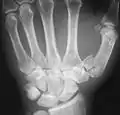

العظم السِنعي الأول أوالعظم السنعي للإبهام هو أول عظم في عظام أصبع الإبهام. ويرتبط مع العظم المربعي في رسغ اليد في أول مفصل رسغي سنعي حتى المفصل السنعي السلامي المرتبط بالعظم السلامي الأدنى.